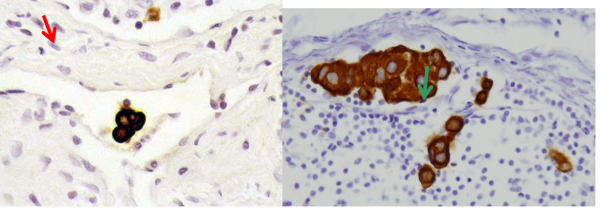

- ניתן להזריק חומר צבע הנספג במערכת הלימפתית וצובע את הבלוטות או חומר רדיואקטיבי המסמן את הבלוטות. בכל מקרה, החומר צריך להיות סגולי, כלומר להיספג רק למערכת הלימפתית. חומר הצבע מוזרק כעשר דקות לפני הניתוח סביב השאת ובניתוח ניתן לראות היטב את כלי הלימפה הצבועים ואת הבלוטות הצבועות (תמונה 51.12).

שיטת בלוטת הזקיף מאפשרת לפתולוג לעבד את הבלוטה בצורה טובה יותר (יותר חתכים) מה שגרם לזיהוי של יותר בלווטת כנגועות. בעיקר עלה שיעור הבלוטות הנגועות המאובחנות כבעלות מיקרו-גרורה (קבוצת תאים שגודלם בין 0.2-2 מ"מ) או על ידי תאים בודדים (קבוצות הקטנות מ- 0.2 מ"מ). הכנסת שיטות אימונוהיסטכימיות לזיהוי תאי אפיתל בבלוטה (צביעות ציטוקרטין – CK) העלה עוד יותר את שיעור הבלוטות הנגועות המאובחנות (תמונה 53.12 ו- 54.12). הסוגיה של המשמעות של תאים בודדים בצביעת ציטוקרטין אינה ברורה, כי הוכח שתאי אפיתל מתים יכולים להמצא גם בבלוטות תקינות, ולכן בשלב זה בלוטות עם גרורות הנראות רק ב-CK - ההתיחסות אליהם היא כאילו אין גרורות. בחולות עם מיקרו–גרורות נמצא שעם המיקרו-גרורה היא בבלוטה אחת, הסיכוי שנמצא עוד בלוטות נגועות הוא כ-15% , אולם ברובם תהייה זו בלוטה עם מיקרו–גרורה. לכן, מוסכם כיום שבחולות עם מיקרו-גרורות אין צורך להמשיך לכריתת מכלול הבלוטות בבית השחי.